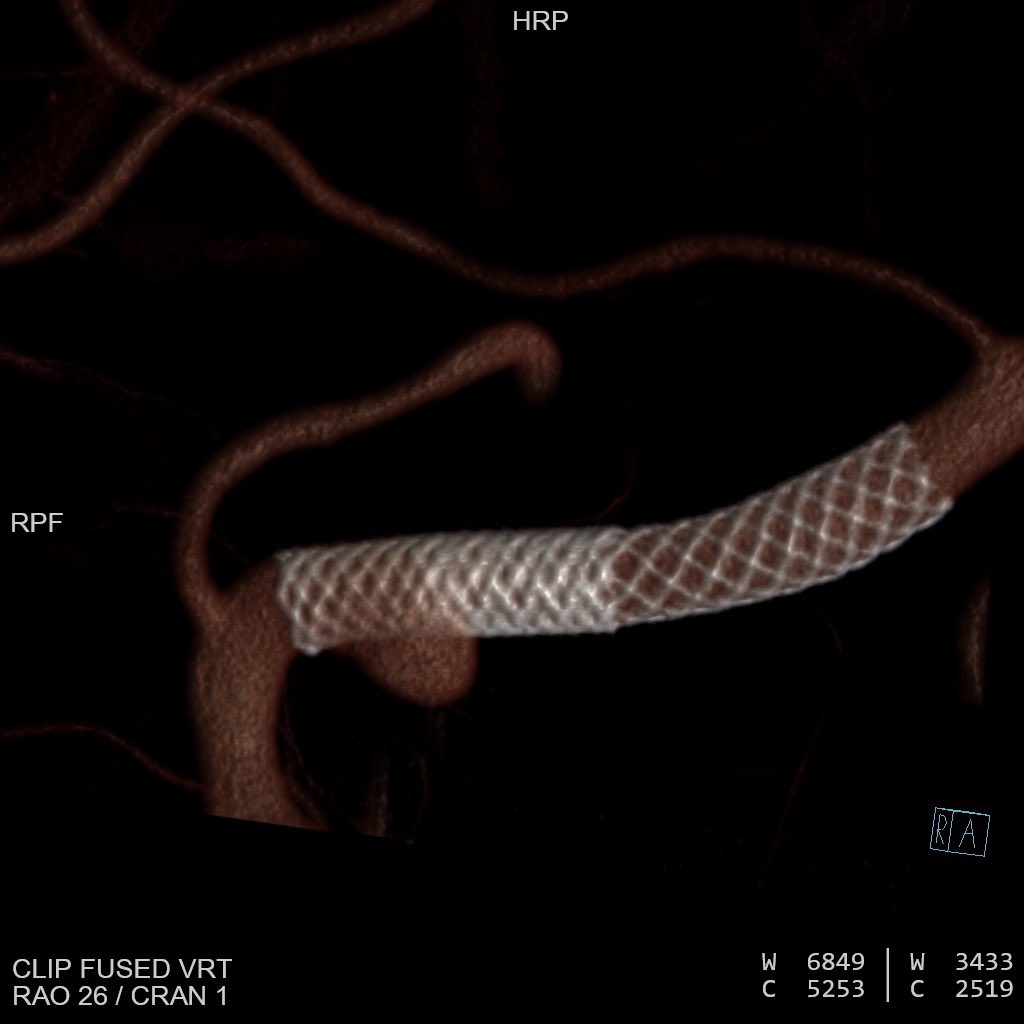

Tumor Workflow: Glomus tympanicum embolization

A case that represents an expansion into a new class of tumor embolization. Planning, imaging, and access from beginning to end.